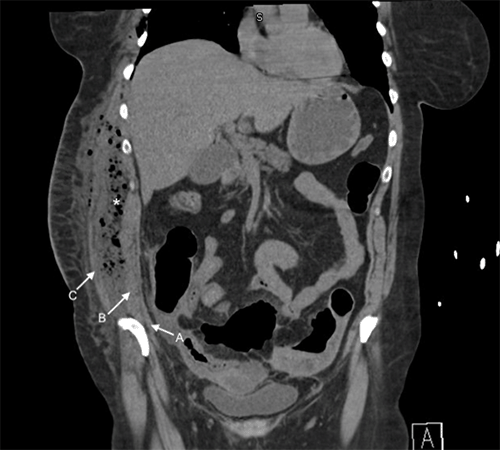

Initial computed tomography (CT) study of the abdomen revealed several large gas and fluid collections in the pelvis, intraperitoneal inflammatory changes in the right lower quadrant, and wall thickening throughout the sigmoid colon with adjacent fluid collections. There was a large 4 × 8 × 14 cm gas and fluid collection in the abdominal wall musculature interposed between the internal and external oblique muscles (Figure 1 and Figure 2). A CT of the thorax revealed extensive gas in the right chest wall with pectoralis, serratus anterior muscle, and subcutaneous tissue involvement, suggesting necrotizing soft tissue infection (Figure 3). Physical exam revealed induration and erythema extending from the right flank to the epigastrium and down to the right lower quadrant without obvious necrotic skin or soft tissue.

Figure 1. Coronal CT Imaging of Abdomen. Published With Permission

Large gas and fluid collection displayed between internal and external oblique muscles along right abdominal wall. Abscess cavity marked by asterisk (*) (A: transversus abdominus; B: internal oblique muscle; C: external oblique muscle)